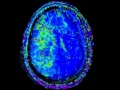

Moyamoya Disease

There are multifocal areas of acute ischemia involving several vascular distributions, most evident in the left greater than right anterior cerebral arterial distribution, as well as in the right middle cerebral artery territory. On time of flight MRA, we see high grade stenosis or occlusion of the carotid terminus on both sides with reconstitution of flow in the more distal vessels via collateralization. This patient had an established diagnosis of moya moya disease, and this case represents a typical imaging presentation of the underlying vasculopathy and ischemic complications.